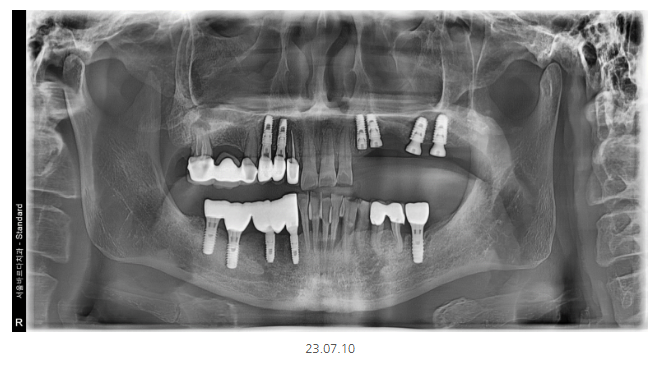

2차 뼈이식과 임플란트 식립한 사진입니다.

5월에 발치 후 2개월 뒤 뼈가 만들어졌을 때

수술을 진행하였습니다.

그리고나서 3개월 뒤

임플란트가 뼈와 잘 붙었음을 확인

임플란트와 머리를 연결하는 중간 기둥을 디자인하였습니다.

상악

그러니까 윗니 어금니 수술 시

평균적으로 3-4개월 정도 기다리는데요.

발치와 동시에 뼈 이식을 해둔 덕분에

3개월 만에 머리를 만들어 드릴 수 있었습니다